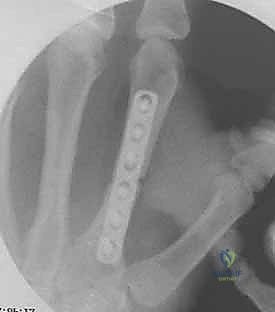

2. التثبيت الداخلي بالصفائح والبراغي المصغرة (Mini-Plates & Screws)

في حالات الكسور المتفتتة (Comminuted) أو الكسور الحلزونية الطويلة التي تميل للانزلاق، يلجأ الدكتور هطيف إلى التثبيت الداخلي المفتوح (ORIF). يتم استخدام صفائح معدنية دقيقة جداً (مصنوعة من التيتانيوم) تتناسب مع حجم عظام اليد.

* الميزة: تثبيت صلب وقوي جداً (Rigid Fixation)، مما يسمح للمريض ببدء العلاج الطبيعي وتحريك أصابعه في اليوم التالي للعملية، وهو أمر بالغ الأهمية لمنع تيبس الأوتار.

خطوات التثبيت الجراحي - توثيق بصري (Intraoperative Imaging)

يحرص الدكتور هطيف على توثيق خطوات العمل الجراحي لضمان أعلى مستويات الدقة. نستعرض هنا مجموعة من الصور من داخل غرفة العمليات توضح مدى تعقيد ودقة هذه الجراحات:

تتطلب الجراحة انتباهاً خاصاً للأوتار الباسطة والقابضة والأعصاب الدقيقة المحيطة بالعظام. استخدام تقنيات الجراحة الميكروسكوبية (Microsurgery) يضمن عدم الإضرار بهذه الأنسجة الحساسة.

معرض الصور الشعاعية: تقييم النتائج الجراحية (Post-Op X-rays)

النجاح الحقيقي يُقاس بالاستعادة المثالية للشكل التشريحي للعظم. توضح هذه الصور الشعاعية بعد الجراحة الدقة المتناهية في إعادة محاذاة العظام وتثبيتها.

التثبيت المحكم يسمح بالشفاء العظمي الأولي (Primary Bone Healing) دون تكوين كتلة عظمية كبيرة (Callus) قد تعيق حركة الأوتار المنزلقة فوقها.